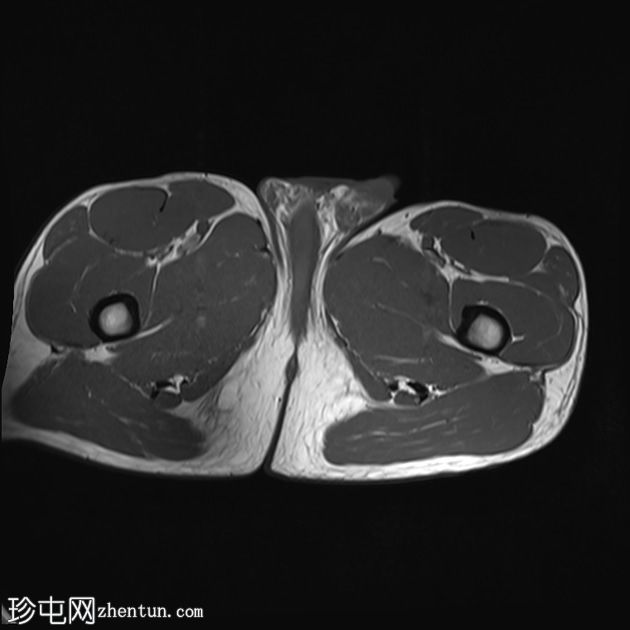

冠状位

T1加权像

股直肌近端和中段前外侧可见一水肿性高信号影,长约15厘米,宽约3厘米。肌纤维轻度分离,但未见撕裂。肌内未见积液;在相邻肌间隙可见一条细小的液线环绕肌肉,延伸至近端肌腱交界处。

股直肌中段的间接肌腱轻度增厚,伴有肌腱周围水肿,提示2B级拉伤。但肌腱保持连续性,骨性附着良好,未见撕裂。